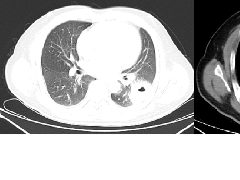

肺隔离症:易误诊为肺癌的占位性病变,肺穿刺禁忌!  肺段与肺内管道应用解剖

肺段与肺内管道应用解剖  肺转移瘤的十种不典型CT表现

肺转移瘤的十种不典型CT表现  肺内淋巴结的CT表现特点及与病理对照

肺内淋巴结的CT表现特点及与病理对照  肺实变与肺不张的CT鉴别诊断